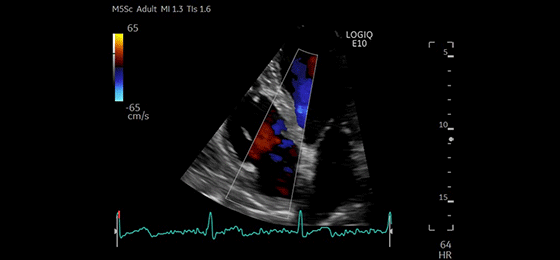

Alax CF Mitral and Aortic Valves, M5Sc-D